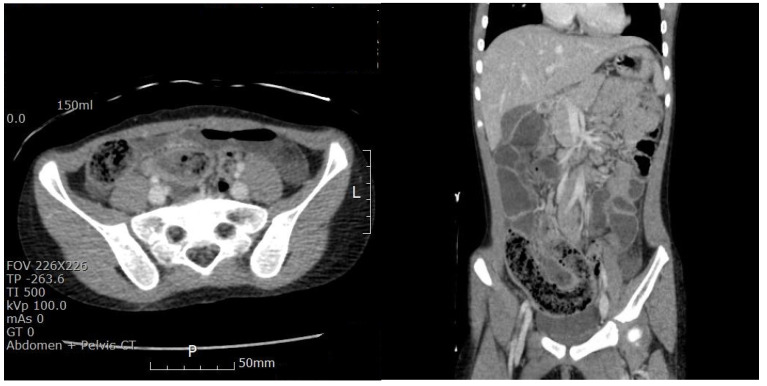

Case presentation: We report the case of a 6-year-old girl who presented to our pediatric emergency center with complaints of acute abdominal pain, vomiting, and diarrhea. She had no notable medical history, including perinatal, surgical, or psychiatric disorders. After finding a bezoar-like structure through a combined enteritis CT scan, reassessing the child's dietary concerns revealed that the child had experienced symptoms of trichophagia for approximately 3 to 4 years. Enterotomy and the removal of the bezoar were successfully performed. A pediatric psychiatric consultation was carried out to prevent further trichophagia-induced complications.